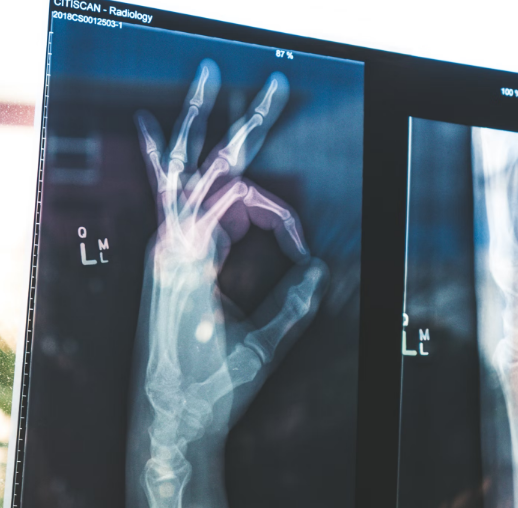

자고 일어났을때 손가락이 붓거나 미약한 통증이 느껴진다면

손가락 관절염의 초기 증상일 수 있습니다.

손가락 관절염의 초기증상

- 통증: 관절 주변에서 불편함이나 통증을 느끼기 시작합니다. 통증은 특히 아침에 심해질 수 있으며, 움직일 때 더 심하게 느껴질 수 있습니다.

- 부기: 손가락 관절이 붓거나 열감이 있을 수 있습니다. 관절 주위에 염증이 생기면 붓는 현상이 나타납니다.

- 뻣뻣함: 관절이 뻣뻣해지고 움직임이 둔해질 수 있습니다. 특히 아침이나 긴 시간 동안 움직이지 않은 후에 증상이 두드러집니다.

- 관절 소리: 손가락을 움직일 때 '딱딱' 소리가 나거나 마찰되는 느낌이 들 수 있습니다.

- 관절 변형: 심한 경우 손가락 관절이 변형되기 시작할 수 있으며, 관절의 기능이 점차 제한됩니다.